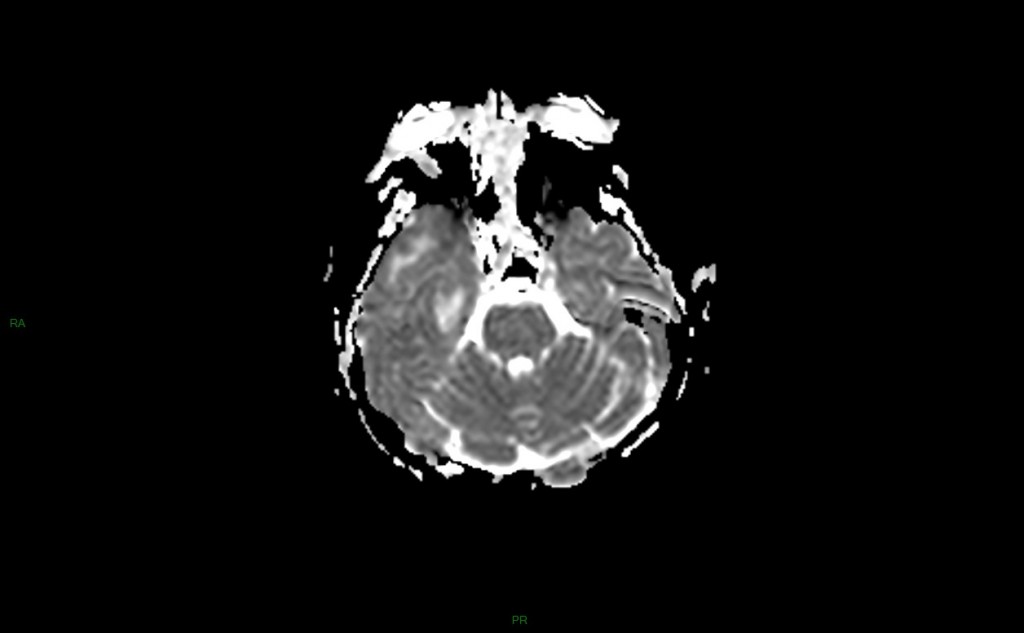

méningo Encéphalite herpétique

• Virus herpex simplex (HSV1)

• 10 à 20 % des encéphalites virales

• Réactivation d’un virus latent du gg trigéminal (de Gasser)

• Syndrome confusionnel fébrile

• Atteinte temporo-limbique

• IRM

• Localisation temporale, temporo-lymbique (cingulum)

• SB et/ou SG

• Epaissisement des gyri, peu d’effet de masse

• Pas de systématisation artérielle

• HypoT1, hyperT2-FLAIR, hyperDiff, ADC variable

• Réhaussement gyriforme après IV

• +++ Respect du putamen +++ (DD avec tumeur)

• Risque : bilatéralisation